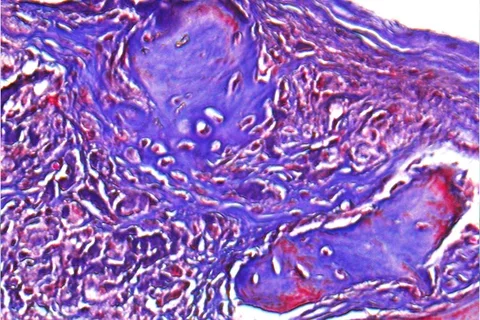

The mouse model had a non-healing skull defect, which the researchers injected with their clay-enhanced hydrogel. After six weeks, they found that the model showed significant bone healing through its own naturally occurring stem cell migration and growth.